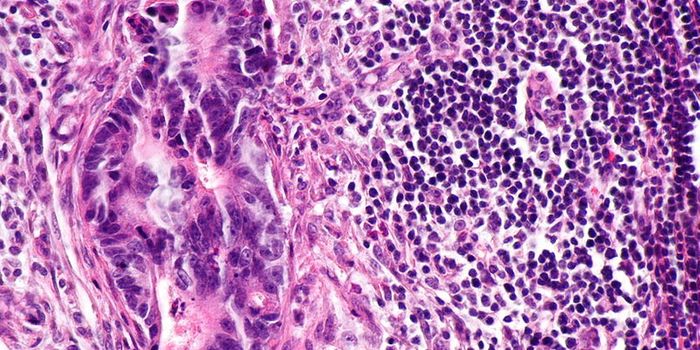

APR 25, 2023CancerRenal cell carcinoma (RCC), also known as kidney cancer, forms in the tubules of the kidney, the part of the organ that ...